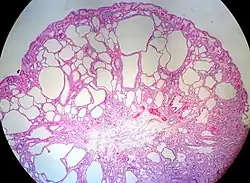

| Juvenile Polyp | Upper GI tract and colon | Cystically dilated glands with expanded lamina propria | Not inherently, may develop dysplasia | ![]() |

Juvenile polyposis syndrome, identical polyps in Cronkhite–Canada syndrome |